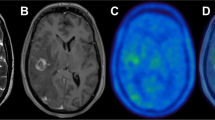

MRI with various sequences (e.g., unenhanced T1-weighted, contrast-enhanced T1-weighted, and T2-weighted sequences with or without the fat suppression option) is another anatomic imaging modality that can complement or sometimes replace CT. MRI has been shown to be more accurate than CT for evaluating the soft tissue or bone extent of nasopharynx, prostate, and brain tumors. However, for pharyngeal–laryngeal tumors, the advantage of MRI over CT has not been confirmed, either in terms of interobserver variability or in terms of target volume delineation.

PET for radiation therapy planning can be used in several ways: visual aid for target delineation, fusion of PET and CT images acquired from separate scanners, or a planning PET-CT scan done on an integrated PET-CT unit with the patient in treatment position. Positioning tools should include a firm flat couch top, immobilization devices, laser beams for patient alignment, and a wide-bore scanner (>70 cm). The PET and CT images thus acquired are complementary as well as supplementary. PET images can identify areas of disease not readily visible on CT alone. CT images can provide improved spatial resolution helping to anatomically localize sites of involvement. Also, the low-noise CT data can be used to generate patient-specific map of attenuation coefficients for correcting PET emission data for errors from photon attenuation, scattered radiation, and other physical degrading factors such as partial volume effect. Thus dual-modality PET-CT can improve both the visual quality and the quantitative accuracy of the correlated radiotracer data. It is now widely accepted and acknowledged that PET-CT impacts significantly on planning in the modern radiation therapy clinic. PET-CT not only has a direct impact on target volume delineation in a wide variety of cancers, but can also lead to a significant change in the therapeutic approach in 10–30 % of patients as compared to other reference imaging modalities (Figs. 18.1, 18.2, and 18.3).

Therapy Planning with Integrated MRI/PET

The combination of MRI and PET in a single gantry for simultaneous acquisition has been developed which has helped to bridge the gap between systems and molecular diagnosis. Both PET and MRI offer richly complementary information about disease. Their integration into a combined system has produced hybrid technology that is significantly better than the sum of its parts. The possibility of using this highly sophisticated hybrid technology for therapy planning is under way and may improve the results further.